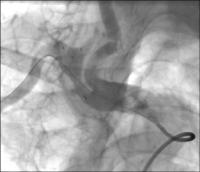

Judkins-Katheter

Abbildung 1: Darstellung der linken Arteria subclavia mit normaler Weite und antegradem Fluß der Arteria vertebralis mittels Judkins-Katheter von transfemoral rechts.